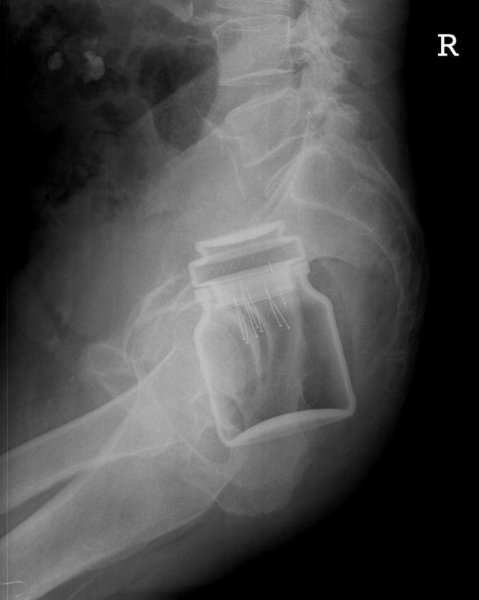

Специалисты по рентгеновской диагностике регулярно сталкиваются с посторонними предметами внутри тела человека. Обычно лишние предметы попадают в пищеварительную систему из-за неосторожности при еде или во время неудачных любовных игр. Почти всё удается вытащить — с хирургическим вмешательством или без него. выбрал самые необычные находки радиологов, которыми они делились на сайте Radiopaedia.org.